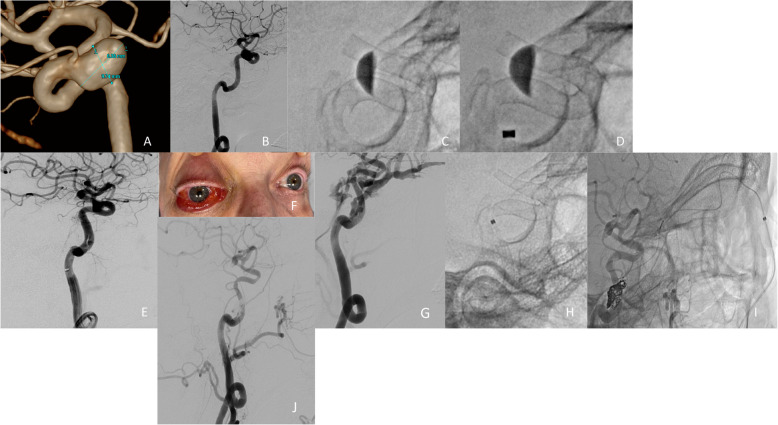

Abstract Image